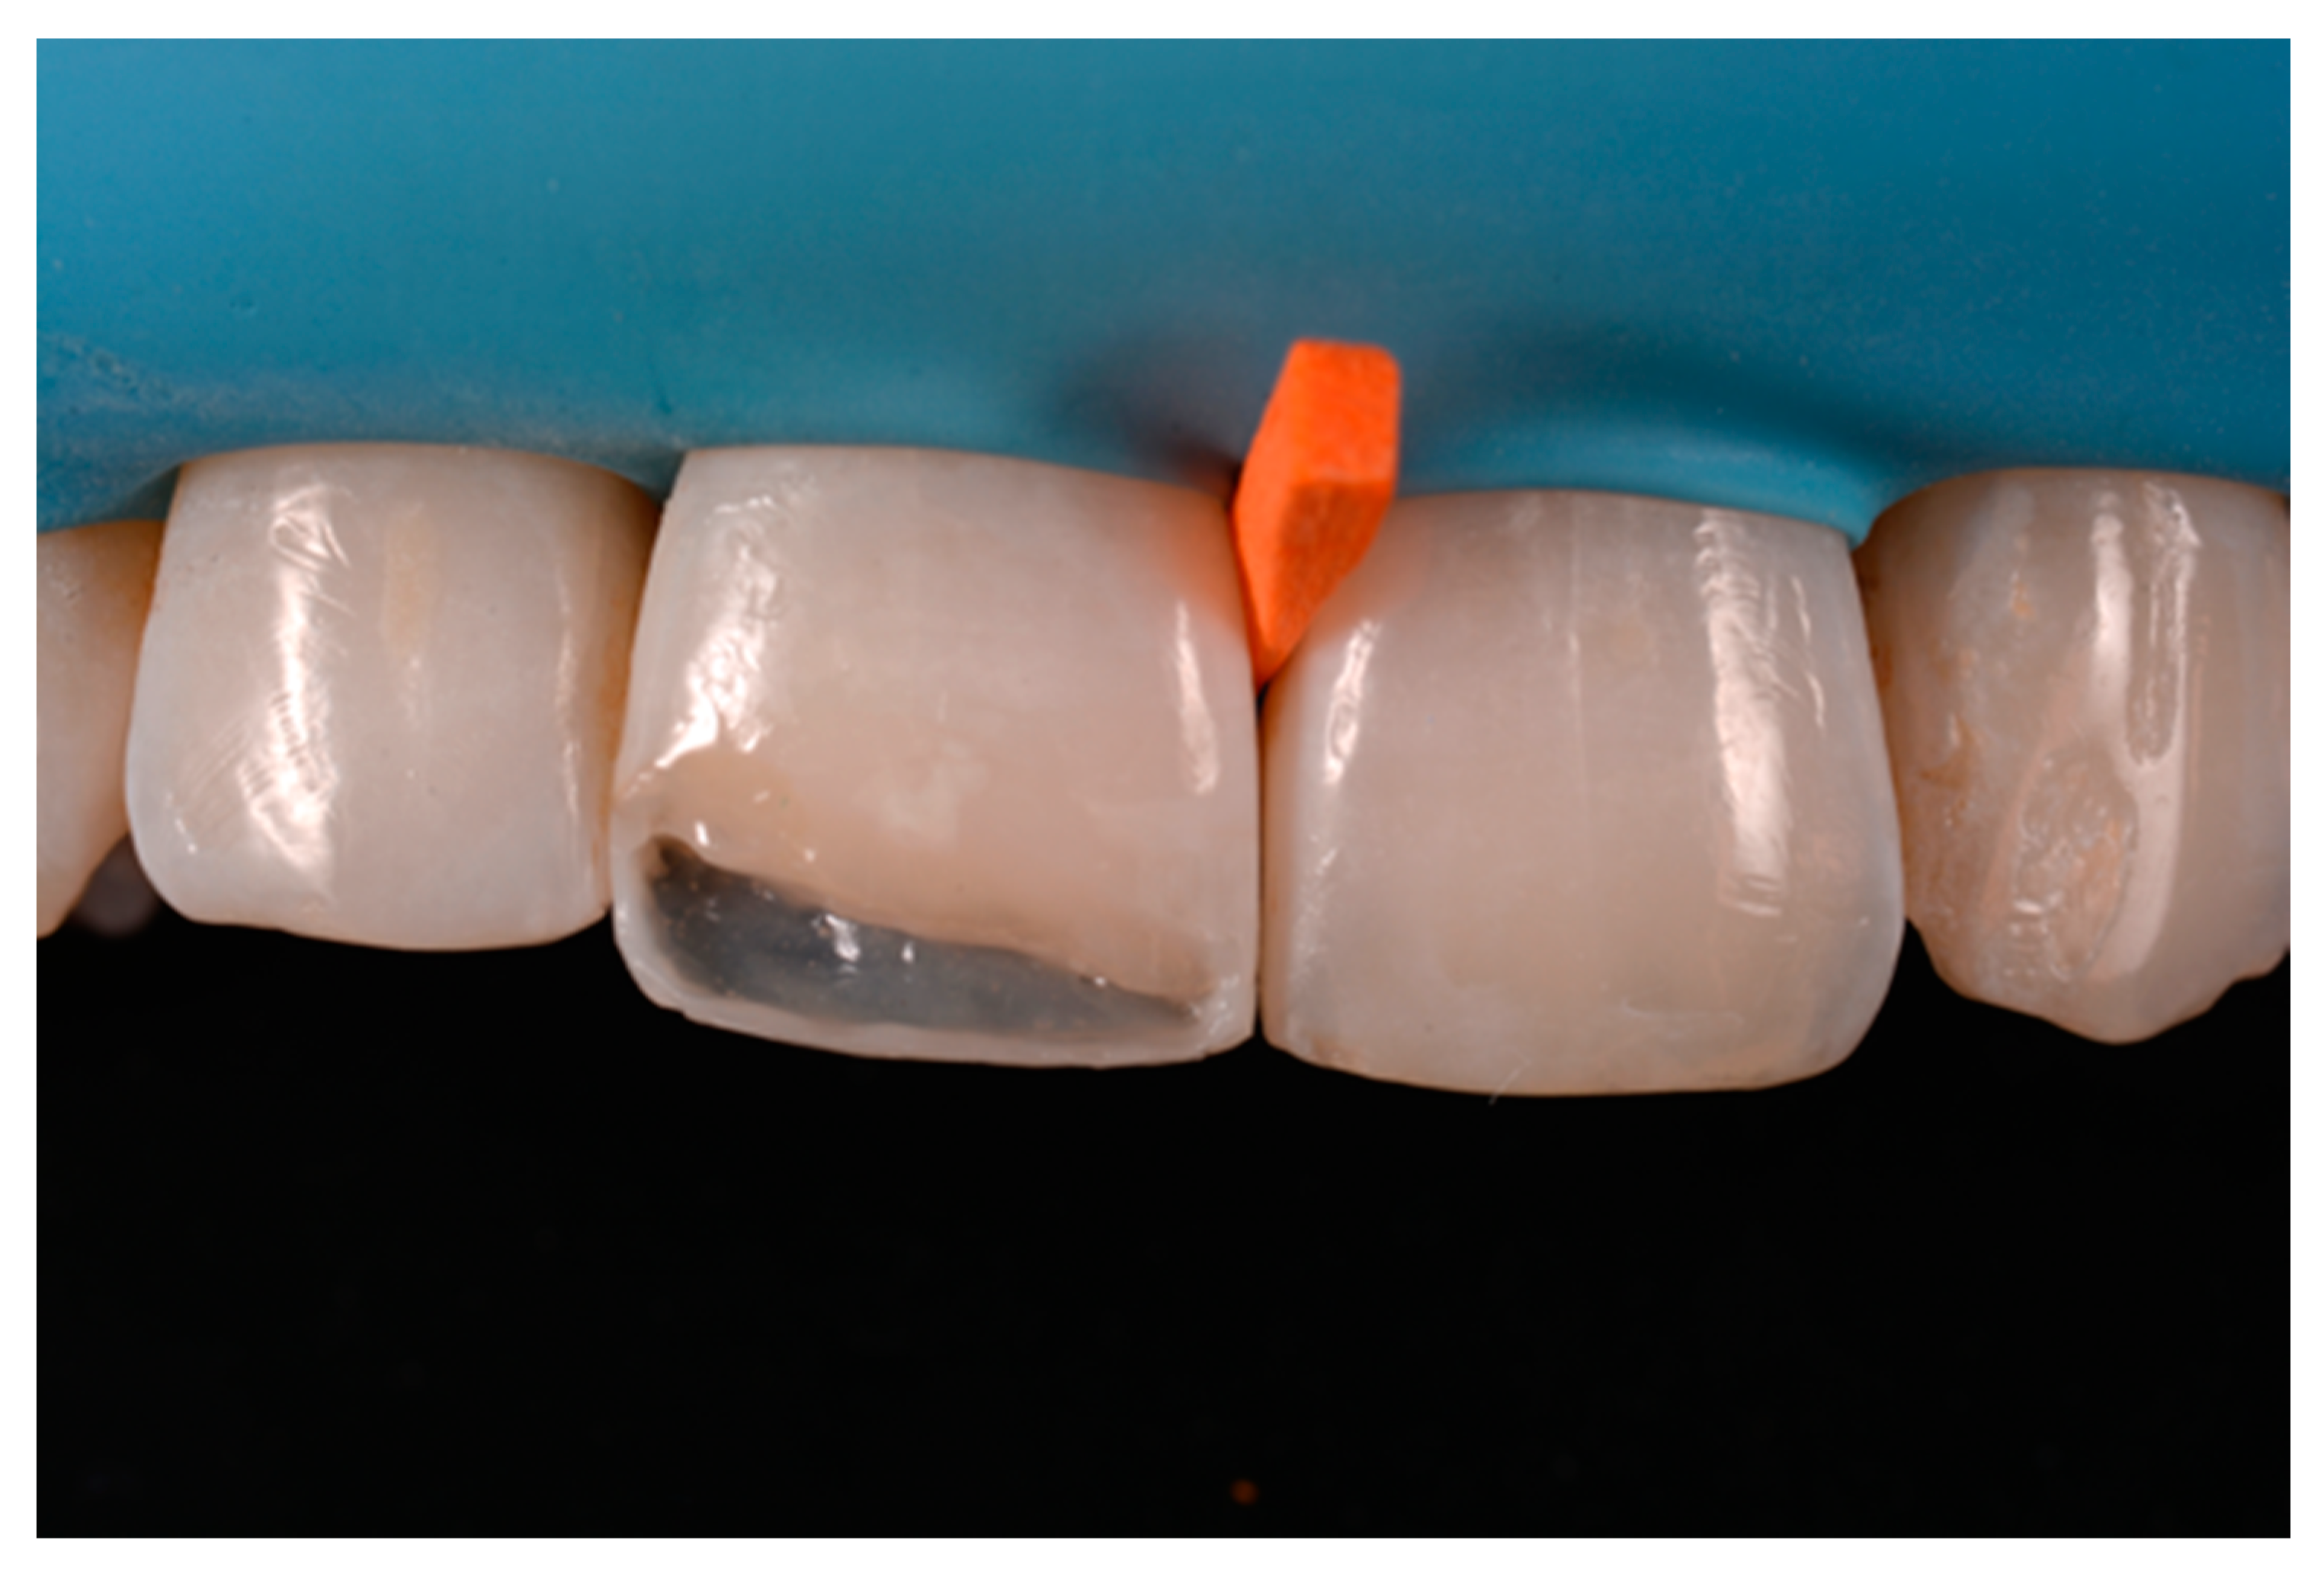

Once completed, the two frames (Clearfil Majesty ES-2, A1E, A2D, Kuraray Noritake Dental, Tokyo, Japan) showed internal and external excesses that were reduced using diamond burs and discs (Figure 33 and Figure 34) strictly following the procedure described in Section 2.1.2 of present article. Excesses were removed from the distal-incisal angle of #2.1 allowing therefore to obtain the desired translucency. After silane application and bonding procedure (Figure 35) as described in Section 2.1.2, restorations were completed (Figure 36 and Figure 37). They both show satisfactory clinical integration 1.5 years post-operative (Figure 38 and Figure 39).

Figure 34.

Frame is also trimmed reducing external outline. Reprinted from Restauri diretti nei settori anteriori, G. Paolone, S. Scolavino, © 2021, with permission from Quintessence Publishing Italy.